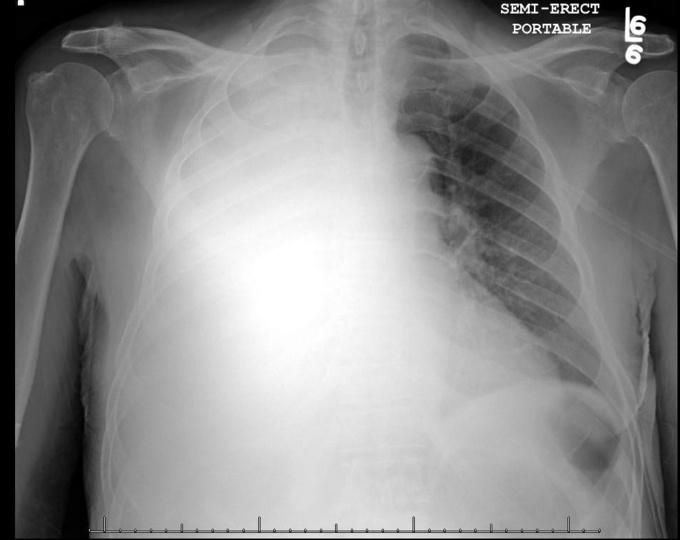

X-quang hai lá phổi một bệnh nhân bị đông đặc. Phần bị hư hại màu trắng mờ, phần màu đen còn có thể hoạt động. Ảnh minh họa

Theo kết quả CT Scan phổi mới nhất cho thấy phổi của bệnh nhân xơ hóa, đông đặc, chỉ còn khoảng 10% hoạt động. Giám đốc bệnh viện cho biết 2 phổi của nam phi công đều rơi vào tình trạng đông đặc, nếu tiếp tục kéo dài tình trạng này sẽ khiến phổi trở thành "ổ dịch" để vi khuẩn sinh sôi mạnh trong cơ thể của nam phi công.